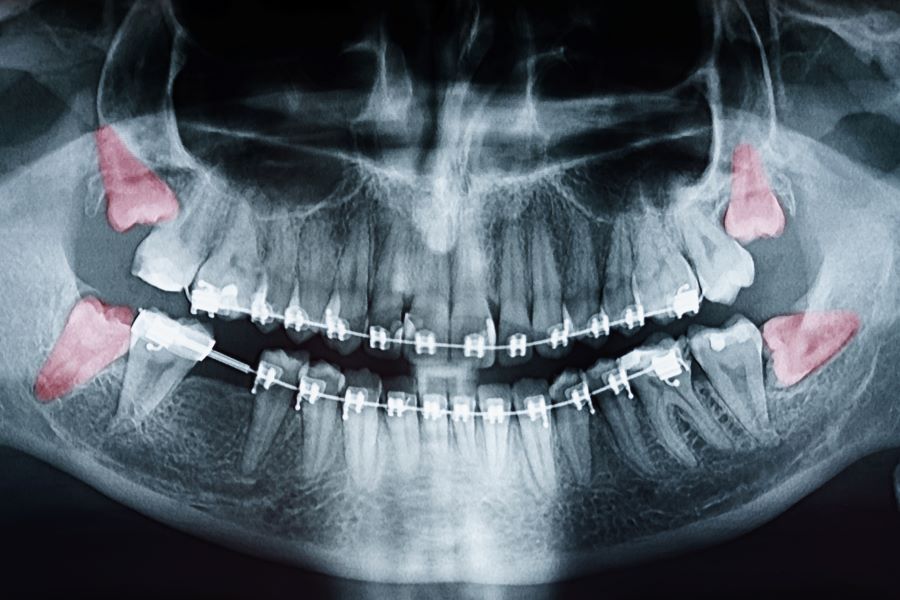

When extracting teeth near nerves, such as lower wisdom teeth, there is a risk of nerve injury.

Symptoms

Numbness or tingling in the tongue, lips, chin, or gums may occur after extraction, particularly if nerves are affected. This loss of sensation can be temporary or, in rare cases, prolonged, requiring medical follow-up to assess progress and consider treatment if necessary.

Maxillary Tuberosity Fracture

When extracting upper molars, a fracture of the maxillary tuberosity may occur, especially if the bone is fragile or the tooth is strongly anchored.

Oro-Sinus Communication

The extraction of upper teeth can sometimes create an opening between the mouth and the maxillary sinus.